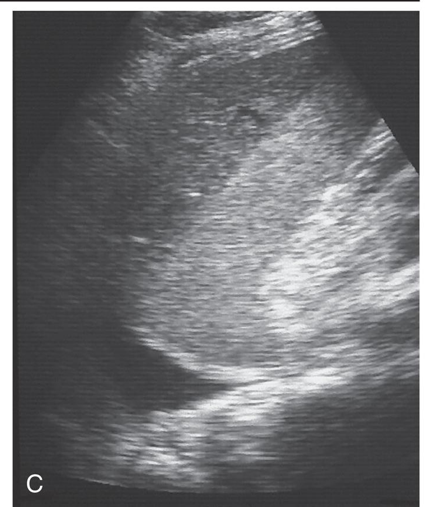

Splenic hematoma: Small hypoechoic separation medial to the splenic capsule represents a splenic hematoma.